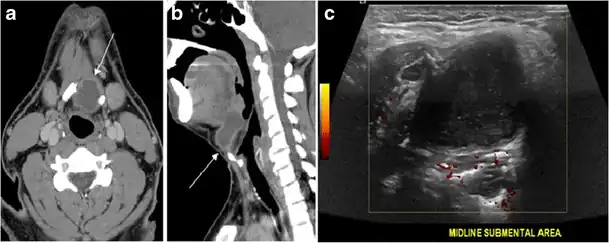

Fig. 19. Long-standing infected thyroglossal duct cyst in a 29-year-old male patient. a Transverse greyscale ultrasound at midline, just above the level of the thyroid gland, shows an oval cystic lesion with internal echoes (white arrows) and posterior enhancement (arrowheads). b Transverse colour Doppler ultrasound shows surrounding peripheral flow (white arrow). c Axial enhanced neck CT scan at the level of the thyroid cartilage demonstrates a slightly off-midline, well-defined, homogeneous cystic lesion embedded in the left strap muscle with peripheral enhancement (white arrow). It shows no calcification or internal enhancement. Thyroid gland was normal (not shown).[1] -

Fig. 20. Recurrent/residual thyroglossal duct cyst in a 39-year-old male patient. The first resection of thyroglossal duct cyst showed histopathology evidence of Hurthle cell type thyroid cancer. However, the second resection showed signs of chronic inflammation, with no malignant cells. a, b Enhanced axial and sagittal neck CT scans demonstrate a unilocular cystic lesion arising from the tongue base and extending through the partially resected hyoid bone. This cystic lesion has a peripheral enhancing wall, which becomes more thick over its inferior aspect associated with surrounding fat stranding at the surgical site (white arrow). There are no internal septations, nodules or masses, or calcifications. c Transverse view of power Doppler ultrasound at the submental area demonstrates cystic lesion and internal debris with no detected internal vascularity.[1] -

Fig. 21. Papillary thyroid carcinoma arising from a thyroglossal duct cyst in a 28-year-old male. an Axial enhanced CT scan shows a large complex cystic lesion (white arrows) adherent to the anterior aspect of the hyoid bone. It has an enhancing mural solid nodules and calcifications (black arrows). There is no cervical lymphadenopathy. b Axial short tau inversion recovery (STIR) MRI image near the same level shows complex lesion of high signal intensity (long white arrows) with solid mural nodules (short white arrow). c Axial fat saturated T1 MRI image post contrast administration shows the complex cystic lesion with thick enhancing wall (long white arrows) and enhancing mural nodules (short white arrows).[1]